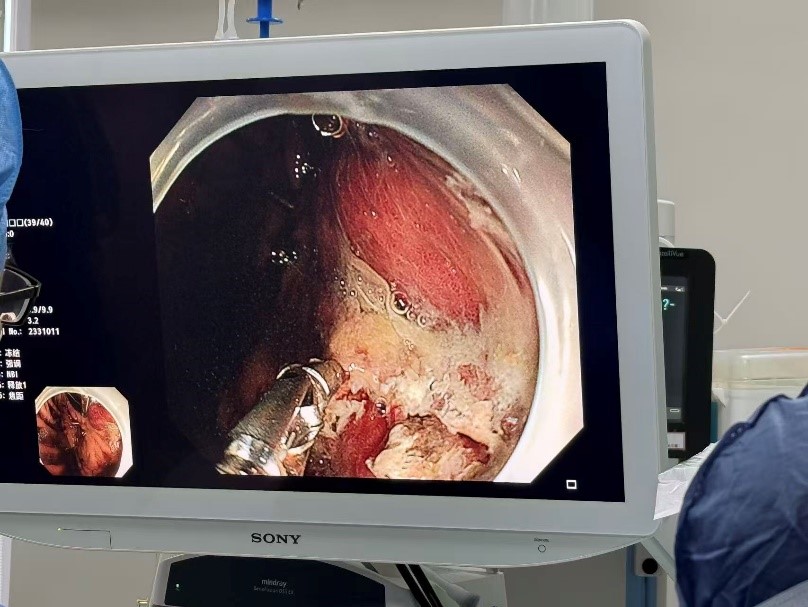

然而,考验接踵而至。韩阿姨突然出现致命的消化道大出血,口鼻和胃肠道不断涌出鲜血,血压难以维持。EICU迅速组织多学科会诊。消化内科医师团队立即施行急诊胃镜,发现了胃小弯侧存在的破口,危急时刻,普外科时林森副主任医师火速驰援,与家属沟通确认后,在ECMO支持下的极高风险中为患者进行胃穿孔修补术。术中清理血凝块达2000ml!术后第二天,患者血压再次持续下降,口鼻和胃肠减压管涌出了大量血液。耳鼻喉科医师在成功压迫患者口腔活动性出血点后,消化内科再次行急诊胃镜,并成功止血。随后,呼吸与危重症医学科曾大雄主任医师团队为患者进行纤支镜检查,吸取了堵塞韩阿姨呼吸道的大量脓痰。